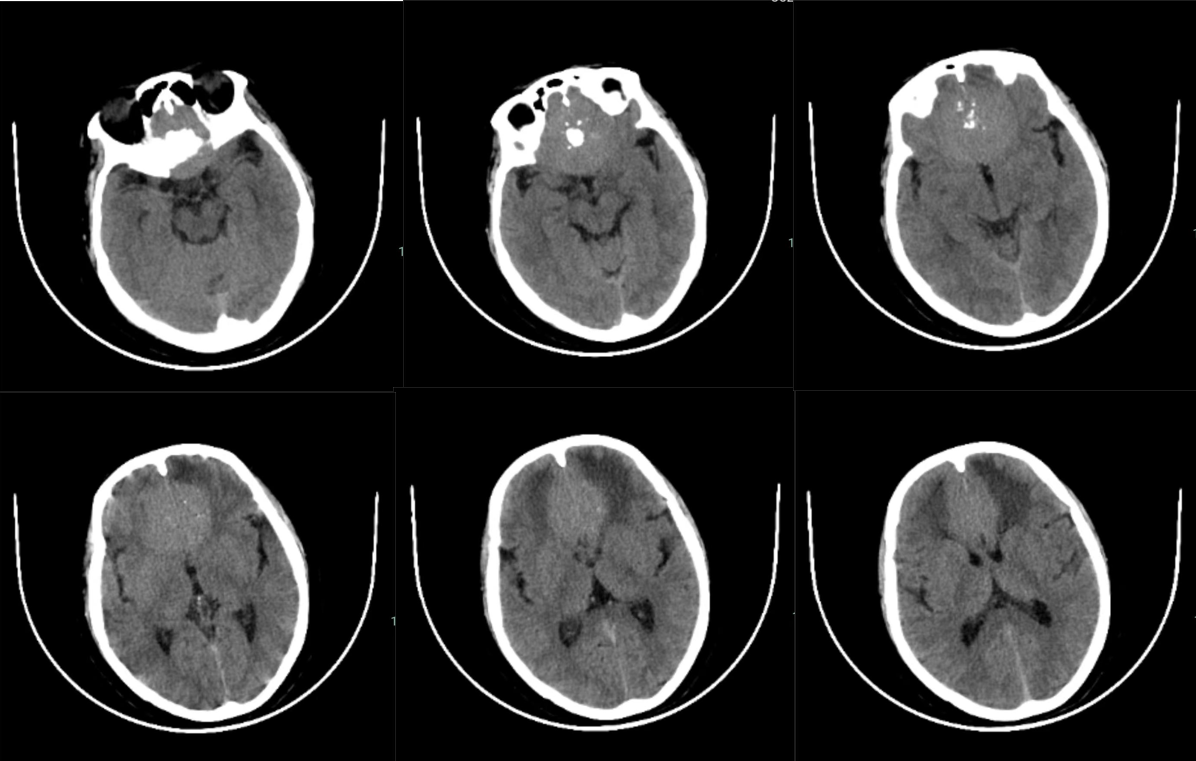

颅脑CT:前颅底占位性病变,颅底骨质增生,瘤内钙化,周围脑组织水肿。

注:术后第一天CT显示额叶脑挫伤及水肿不重